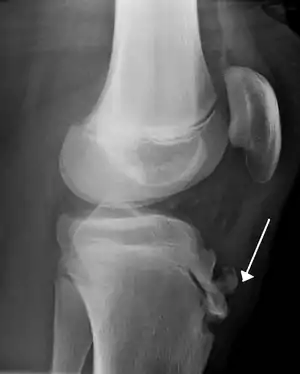

| Lateral radiograph of the knee demonstrating fragmentation of the tibial tubercle with overlying soft tissue swelling. | |

-رادیوگرافی برجسته شدن و گاهی قطعه قطعه شدن برجستگی درشتنی را نشان میدهد.